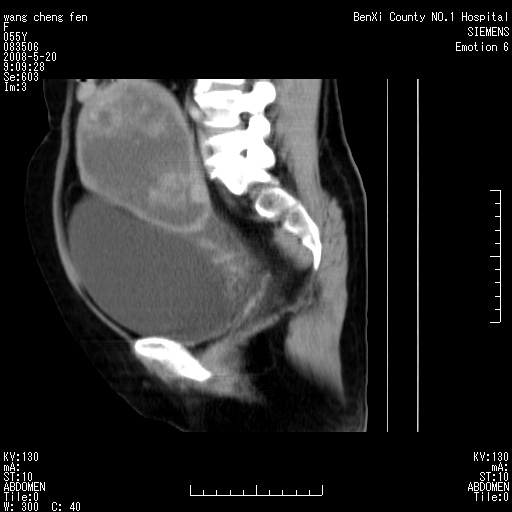

女、绝经后阴道流血3个月

左侧附件区巨大囊实性病灶,边缘光整,病灶囊壁较厚,增强示囊壁及实性部分明显强化,强化呈度与宫体实质大致相同,宫腔积液征像,未见盆腔积液等其他异常,考虑左侧卵巢囊腺癌,不除外囊腺瘤及浆膜下肌瘤坏死

左侧附件区巨大囊实性病灶,边缘光整,病灶囊壁较厚,增强示囊壁及实性部分明显强化,强化呈度与宫体实质大致相同,宫腔积液征像,未见盆腔积液等其他异常。绝经后阴道流血3个月,结合病史左侧卵巢囊腺癌首先考虑,宫腔扩大不除外累及。期待结果。

考虑巨大的浆膜下子宫肌瘤并变性坏死,宫颈周围静脉曲张。

1,宫颈部占位,宫颈癌?2,左侧附件区囊实性占位,界较清,实质部分强化明显。考虑浆膜下或阔韧带肌瘤囊变可能大。囊腺类肿瘤不除外。